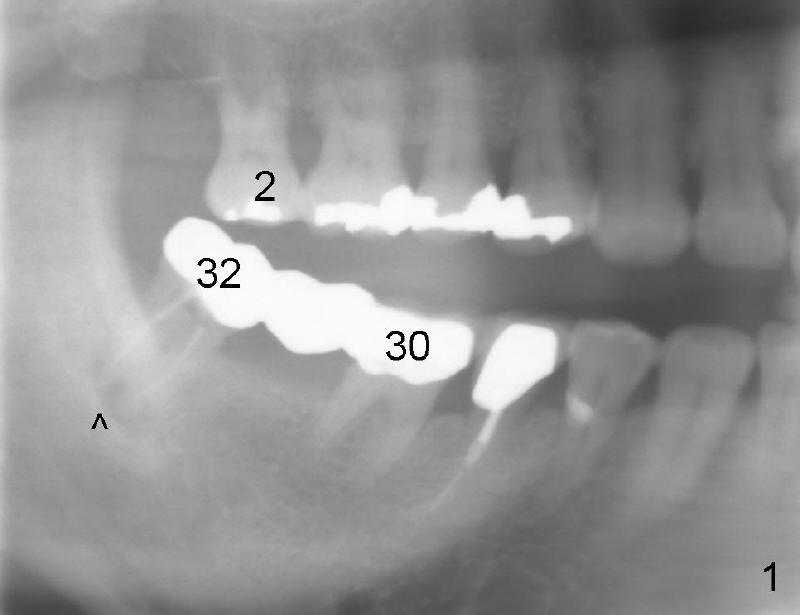

Magnification of Fig. 1 (panoramic x-ray) shows that #32 is nonfunctional partially and it has periapical radiolucency (<). Return to main text